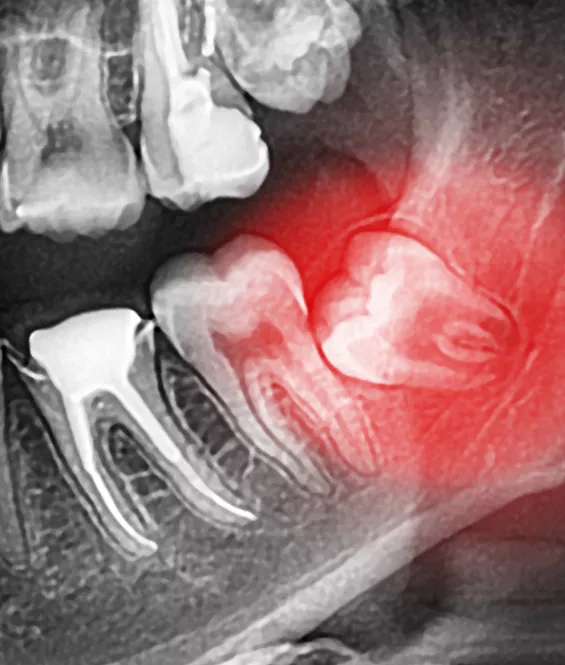

The wisdom teeth are a third set of large molars. They are usually the last of the adult teeth to grow in. For many patients, there is no room in the jaw for the wisdom teeth to emerge correctly, and they can become impacted or misaligned. If we detect that this is happening, we will recommend extraction of the wisdom teeth before they erupt through the gums.

Because the wisdom teeth are usually removed before they erupt, removal is usually a surgical procedure where the teeth are removed through incisions in the gums. The procedure is usually performed under local anesthetic or mild sedation. After the procedure, the incisions are closed with sutures.